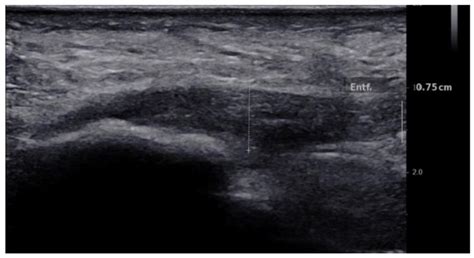

• plantar fascia injection ultrasound

• ultrasound guided plantar fascia injection